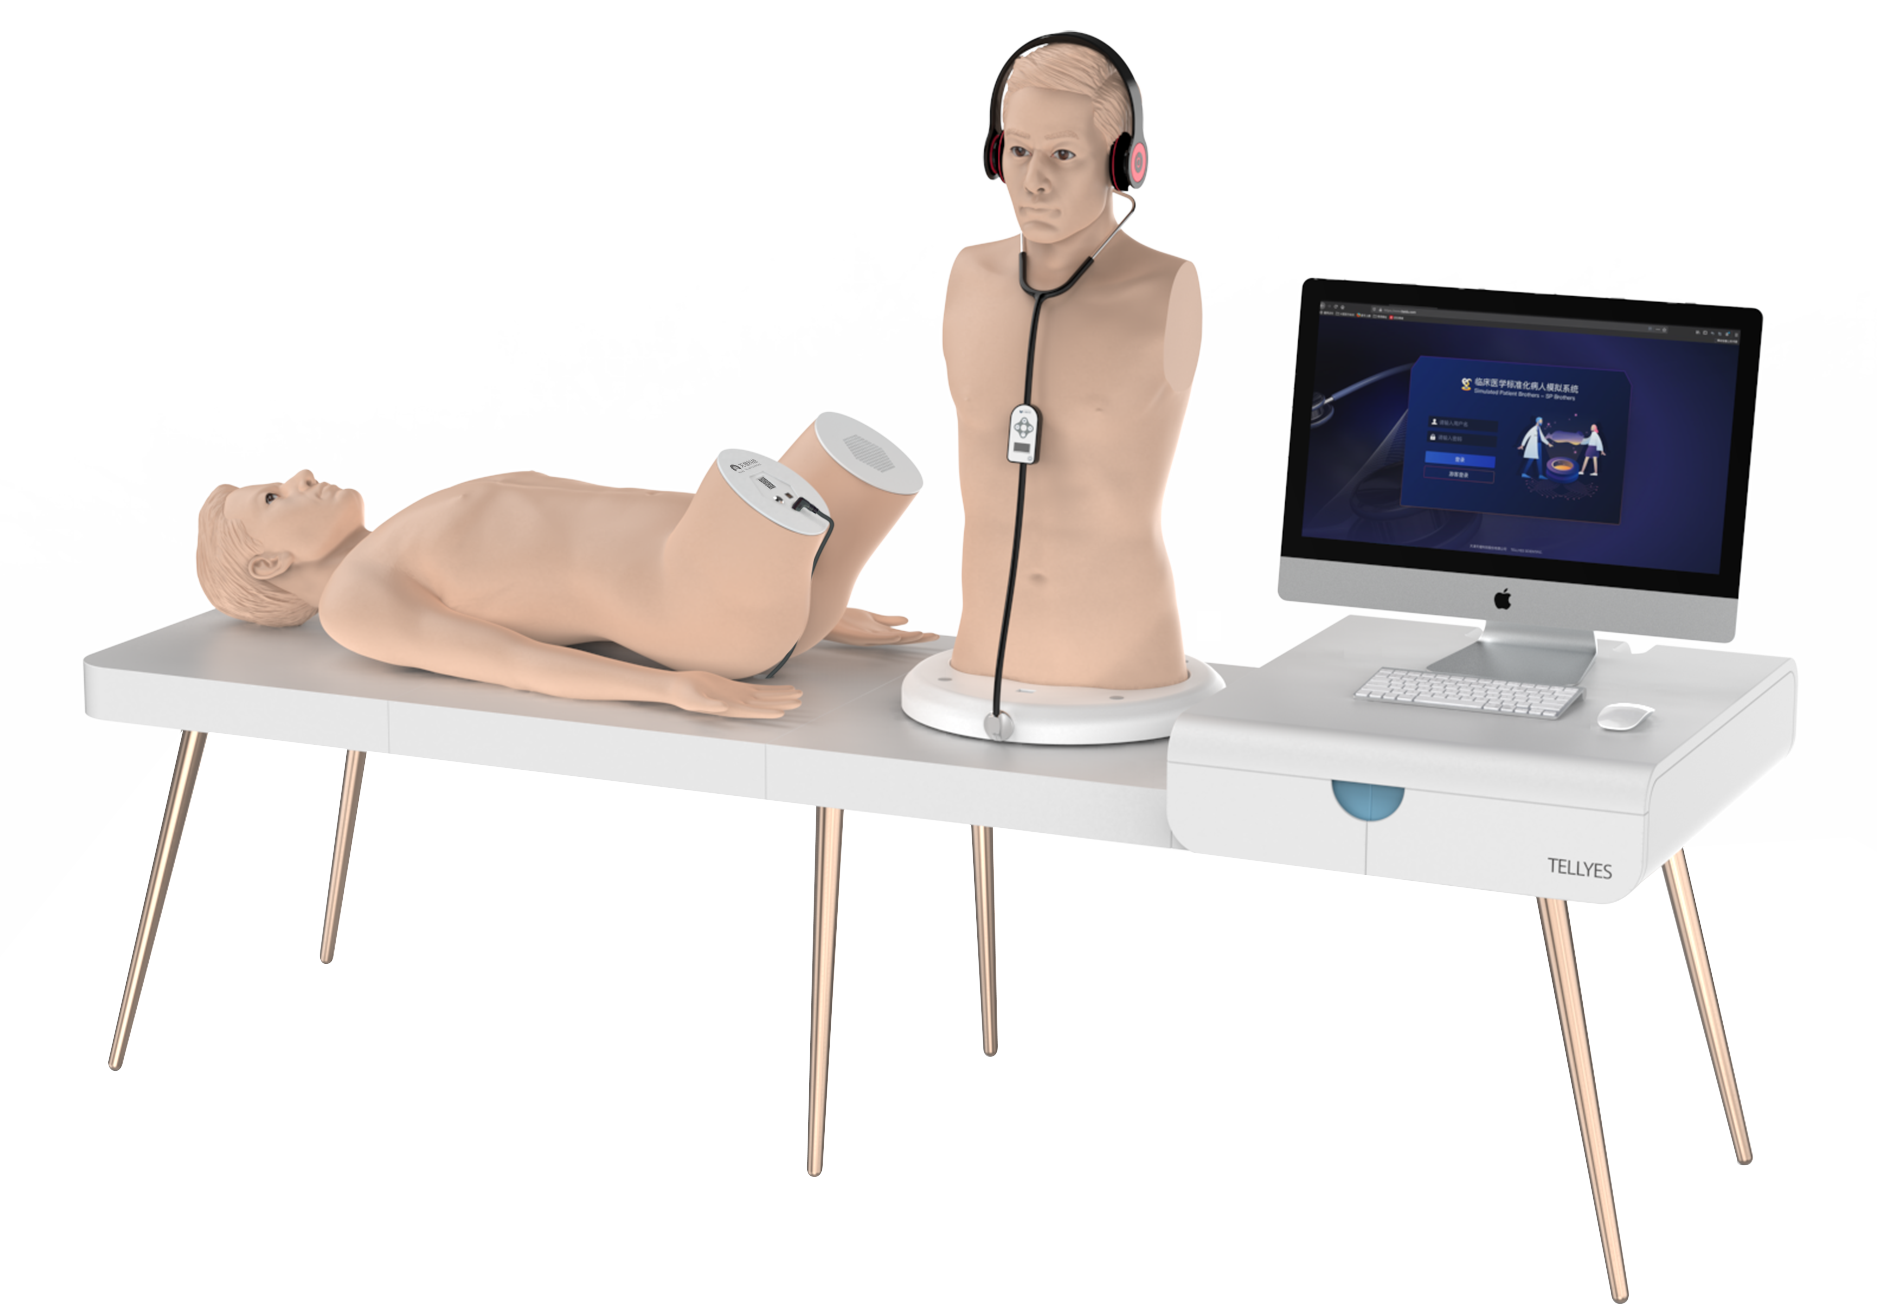

Hands-on Training Zone

Combined high fidelity models and smart interactive systems, this zone intends to recreate clinical scenarios and establish a dual-dimensional training system for clinical skills and critical thinking to advance medical talent cultivation, covering full-chain nursing skill training and clinical decision making. It explores new frontiers in AI-powered medical education, pushing the boundaries of technology-driven medical education!

SP Brothers-Standardized Patient Brothers